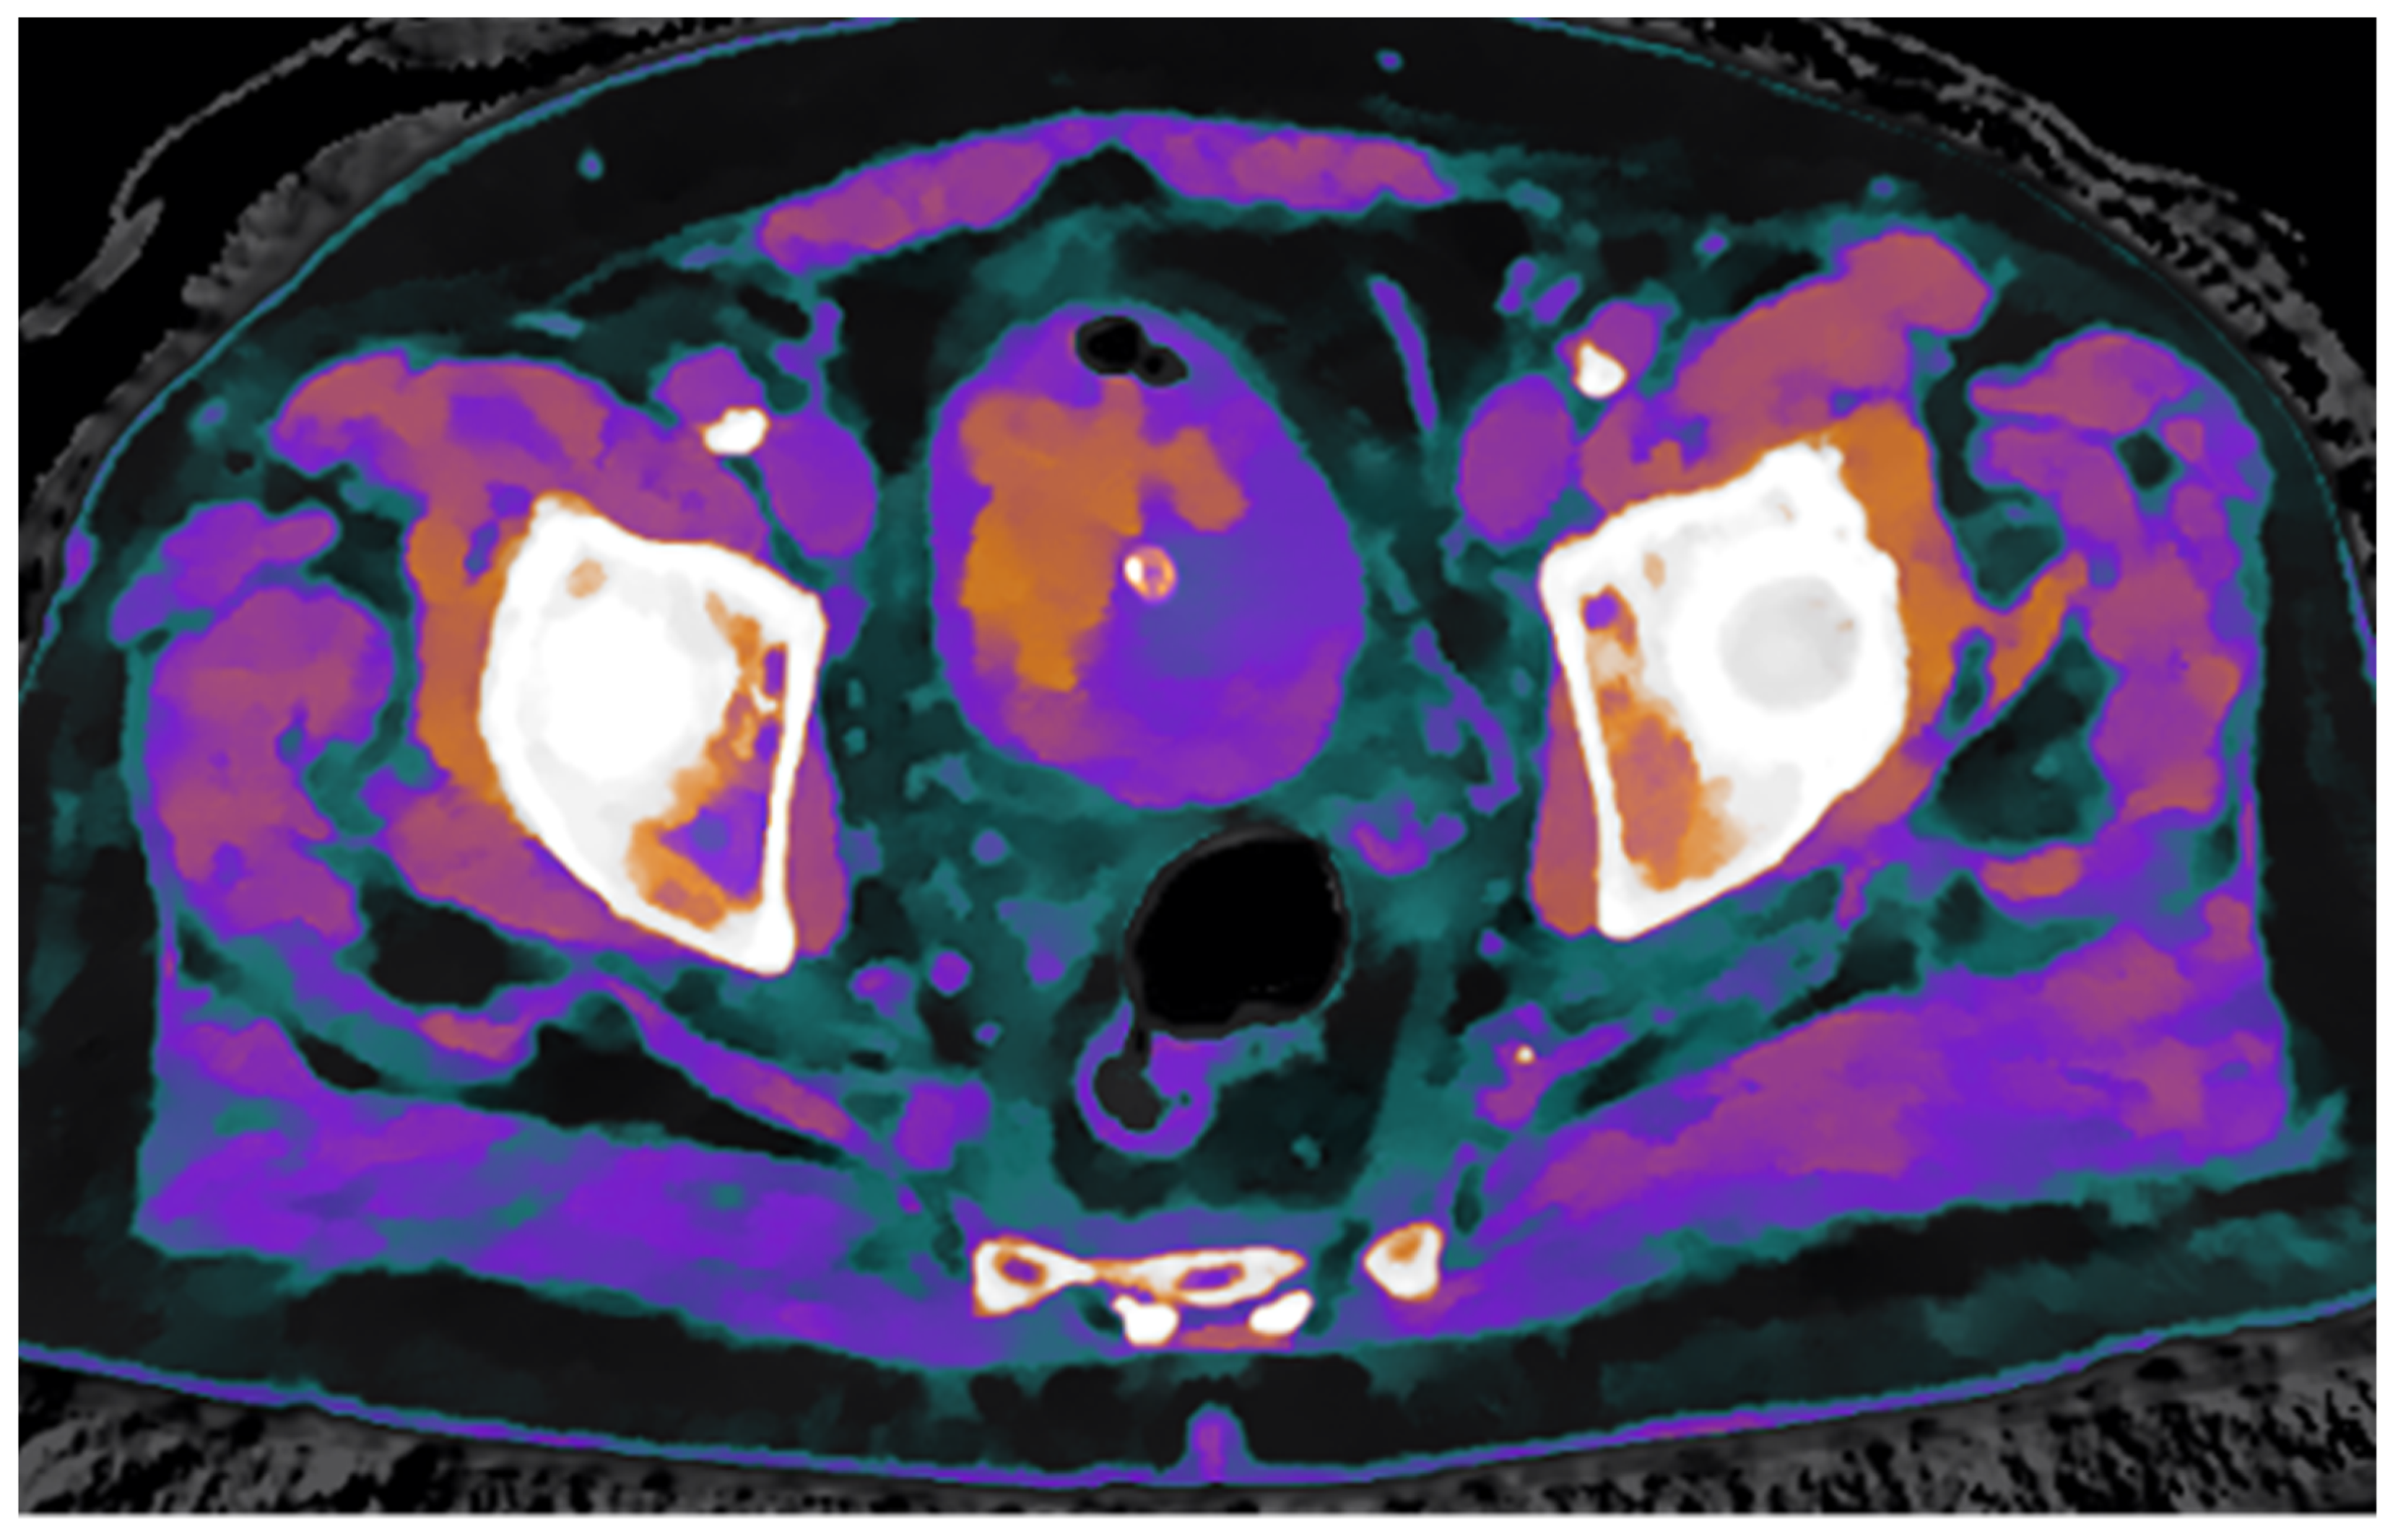

In this case, the iodine map overlaid on the conventional venous phase image demonstrates clear increased iodine uptake in two foci along the left posterolateral bladder wall and in two minute foci along the anterior wall, findings consistent with hypervascular neoplastic tissue. In contrast, the intraluminal hyperdense mass, visible on the unenhanced scan, shows no significant iodine uptake, supporting the diagnosis of a non-enhancing structure, most likely a thrombus (Figure 3).

To further confirm the differing structural composition of the two tissue types, additional spectral maps were utilized. Specifically, the Z-effective map, based on the effective atomic number, combined with the electron density map, reflecting tissue electron composition, enabled a clear distinction between thrombotic and neoplastic tissue based on their unique physical properties (Figure 4).

Figure 3. The iodine density map overlaid on venous phase CT images shows increased iodine uptake in the posterolateral left bladder wall and in two foci of the anterior wall, findings indicative of metabolically active neoplastic areas. In contrast, the mass in the right anterolateral wall demonstrates no iodine uptake, consistent with a non-metabolically active lesion, suggestive of thrombus.

Figure 4. Fusion of Z-effective and electron density maps from the non-enhanced scan demonstrates an endoluminal thrombus with its characteristic structural features.